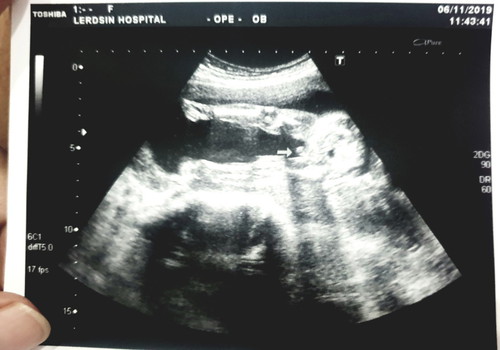

ซาวน์ตอน20วีค เห่นชัดมากป๊าเค้าดีใจใหญ่เรย ได้ผช.สมดั่งใจเค้า ??